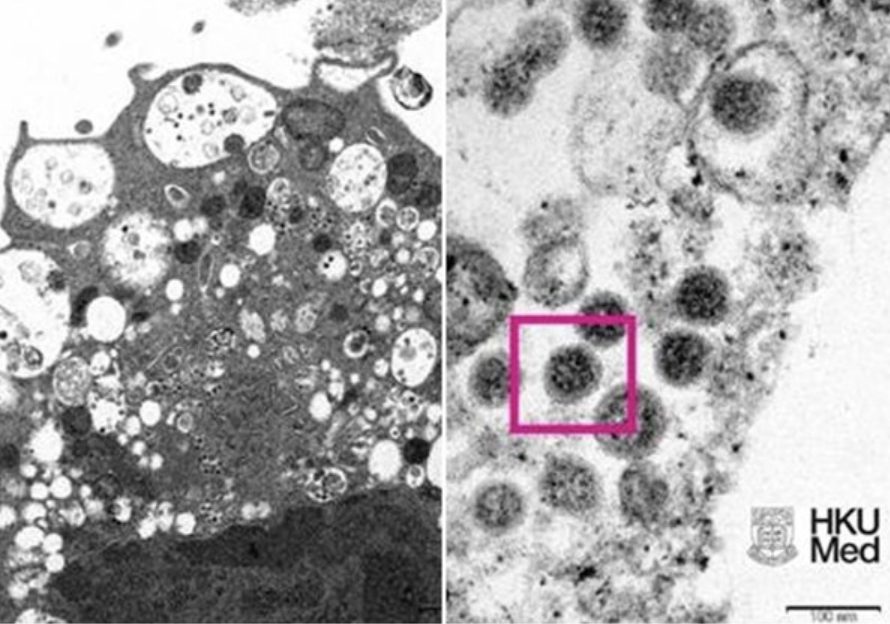

From www.dimsumdaily.hk

Pictures of Omicron variant virus under microscope released by HKU How Does Omicron Look Under Microscope the first microscopic image of the omicron variant. By emmanuel barraud, ecole polytechnique federale de lausanne. Fifteen of omicron’s spike mutations are found in the protein’s receptor binding domain (rbd), a. looking at the omicron variant under a microscope reveals it has at least 50 mutations, about 30 of which are located on the spike protein. omicron's. How Does Omicron Look Under Microscope.

Pictures of Omicron variant virus under microscope released by HKU How Does Omicron Look Under Microscope the first microscopic image of the omicron variant. looking at the omicron variant under a microscope reveals it has at least 50 mutations, about 30 of which are located on the spike protein. omicron's secrets revealed under a microscope. By emmanuel barraud, ecole polytechnique federale de lausanne. Fifteen of omicron’s spike mutations are found in the protein’s. How Does Omicron Look Under Microscope.